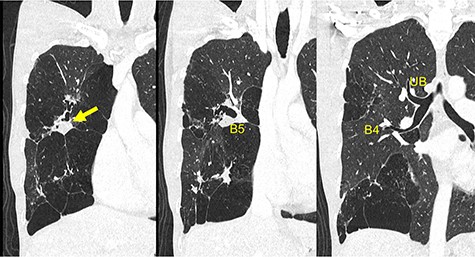

A 30-year-old man was referred to our hospital for further examination due to an abnormal shadow on chest radiography taken when he was 23 years old. Chest computed tomography (CT) revealed right B5 occlusion. Bronchoscopy showed no bifurcation in the region where the right B5 should be located. These findings are consistent with the diagnosis of bronchial atresia. Because he was not experiencing any symptoms, he refused to undergo surgical resection. Seven years later, he presented with right chest pain suggestive of an infectious complication. Antibiotic therapy resolved the infection. Following this, he was referred to our department for surgical intervention. He was a never-smoker and his medical history was unremarkable for other conditions. Laboratory examinations revealed that the patient had normal liver and renal function with no elevation of inflammatory markers (white blood cell count: 6860/μl; C-reactive protein: <0.30 mg/dl). Although carcinoembryonic antigen was within normal ranges (2.7 U/ml; normal range < 5.0 U/ml), cancer antigen 19-9 was elevated (291.8 U/ml; normal range < 37 U/ml). Chest radiography revealed an infiltration shadow with a partial hyperlucency in the right upper and lower lung fields. Chest CT showed B5 bronchial occlusion, mucoid impaction and emphysematous changes distributed throughout the right middle lobe and S3 segment of the right upper lobe (Fig. 1).

Preoperative chest CT demonstrates a mucinous impaction (Arrow) and blind-end of B5. CT, computed tomography; B, bronchus; UB, upper bronchus.